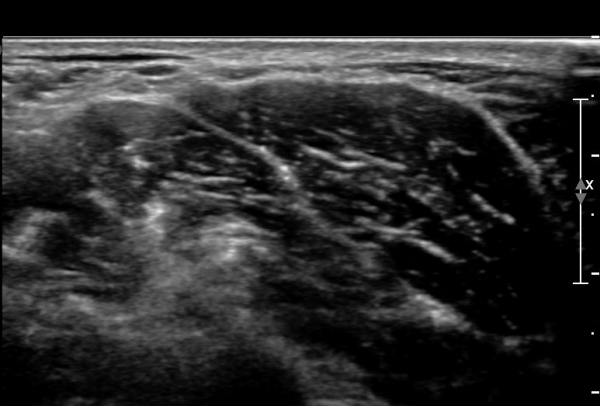

ŽÃÊÀÚ¸¦ ¾à°£ ¸»´ÜÀ¸·Î À̵¿ÇÏ´Ï ¼ö¼ú ¹ÝÈçÀÌ °üÂûµÇ°í  ¼ö¼ú¹ÝÈç ÈÄ¹æ ½ÉºÎ¿¡¼­

ôÃߺνŰæÀÌ °üÂûµÇ´Âµ¥ ½Å°æÀÇ ¿¬¼Ó¼ºÀº À¯ÁöµÇ¾î ÀÖ´Ù(»çÁø 4, 5).